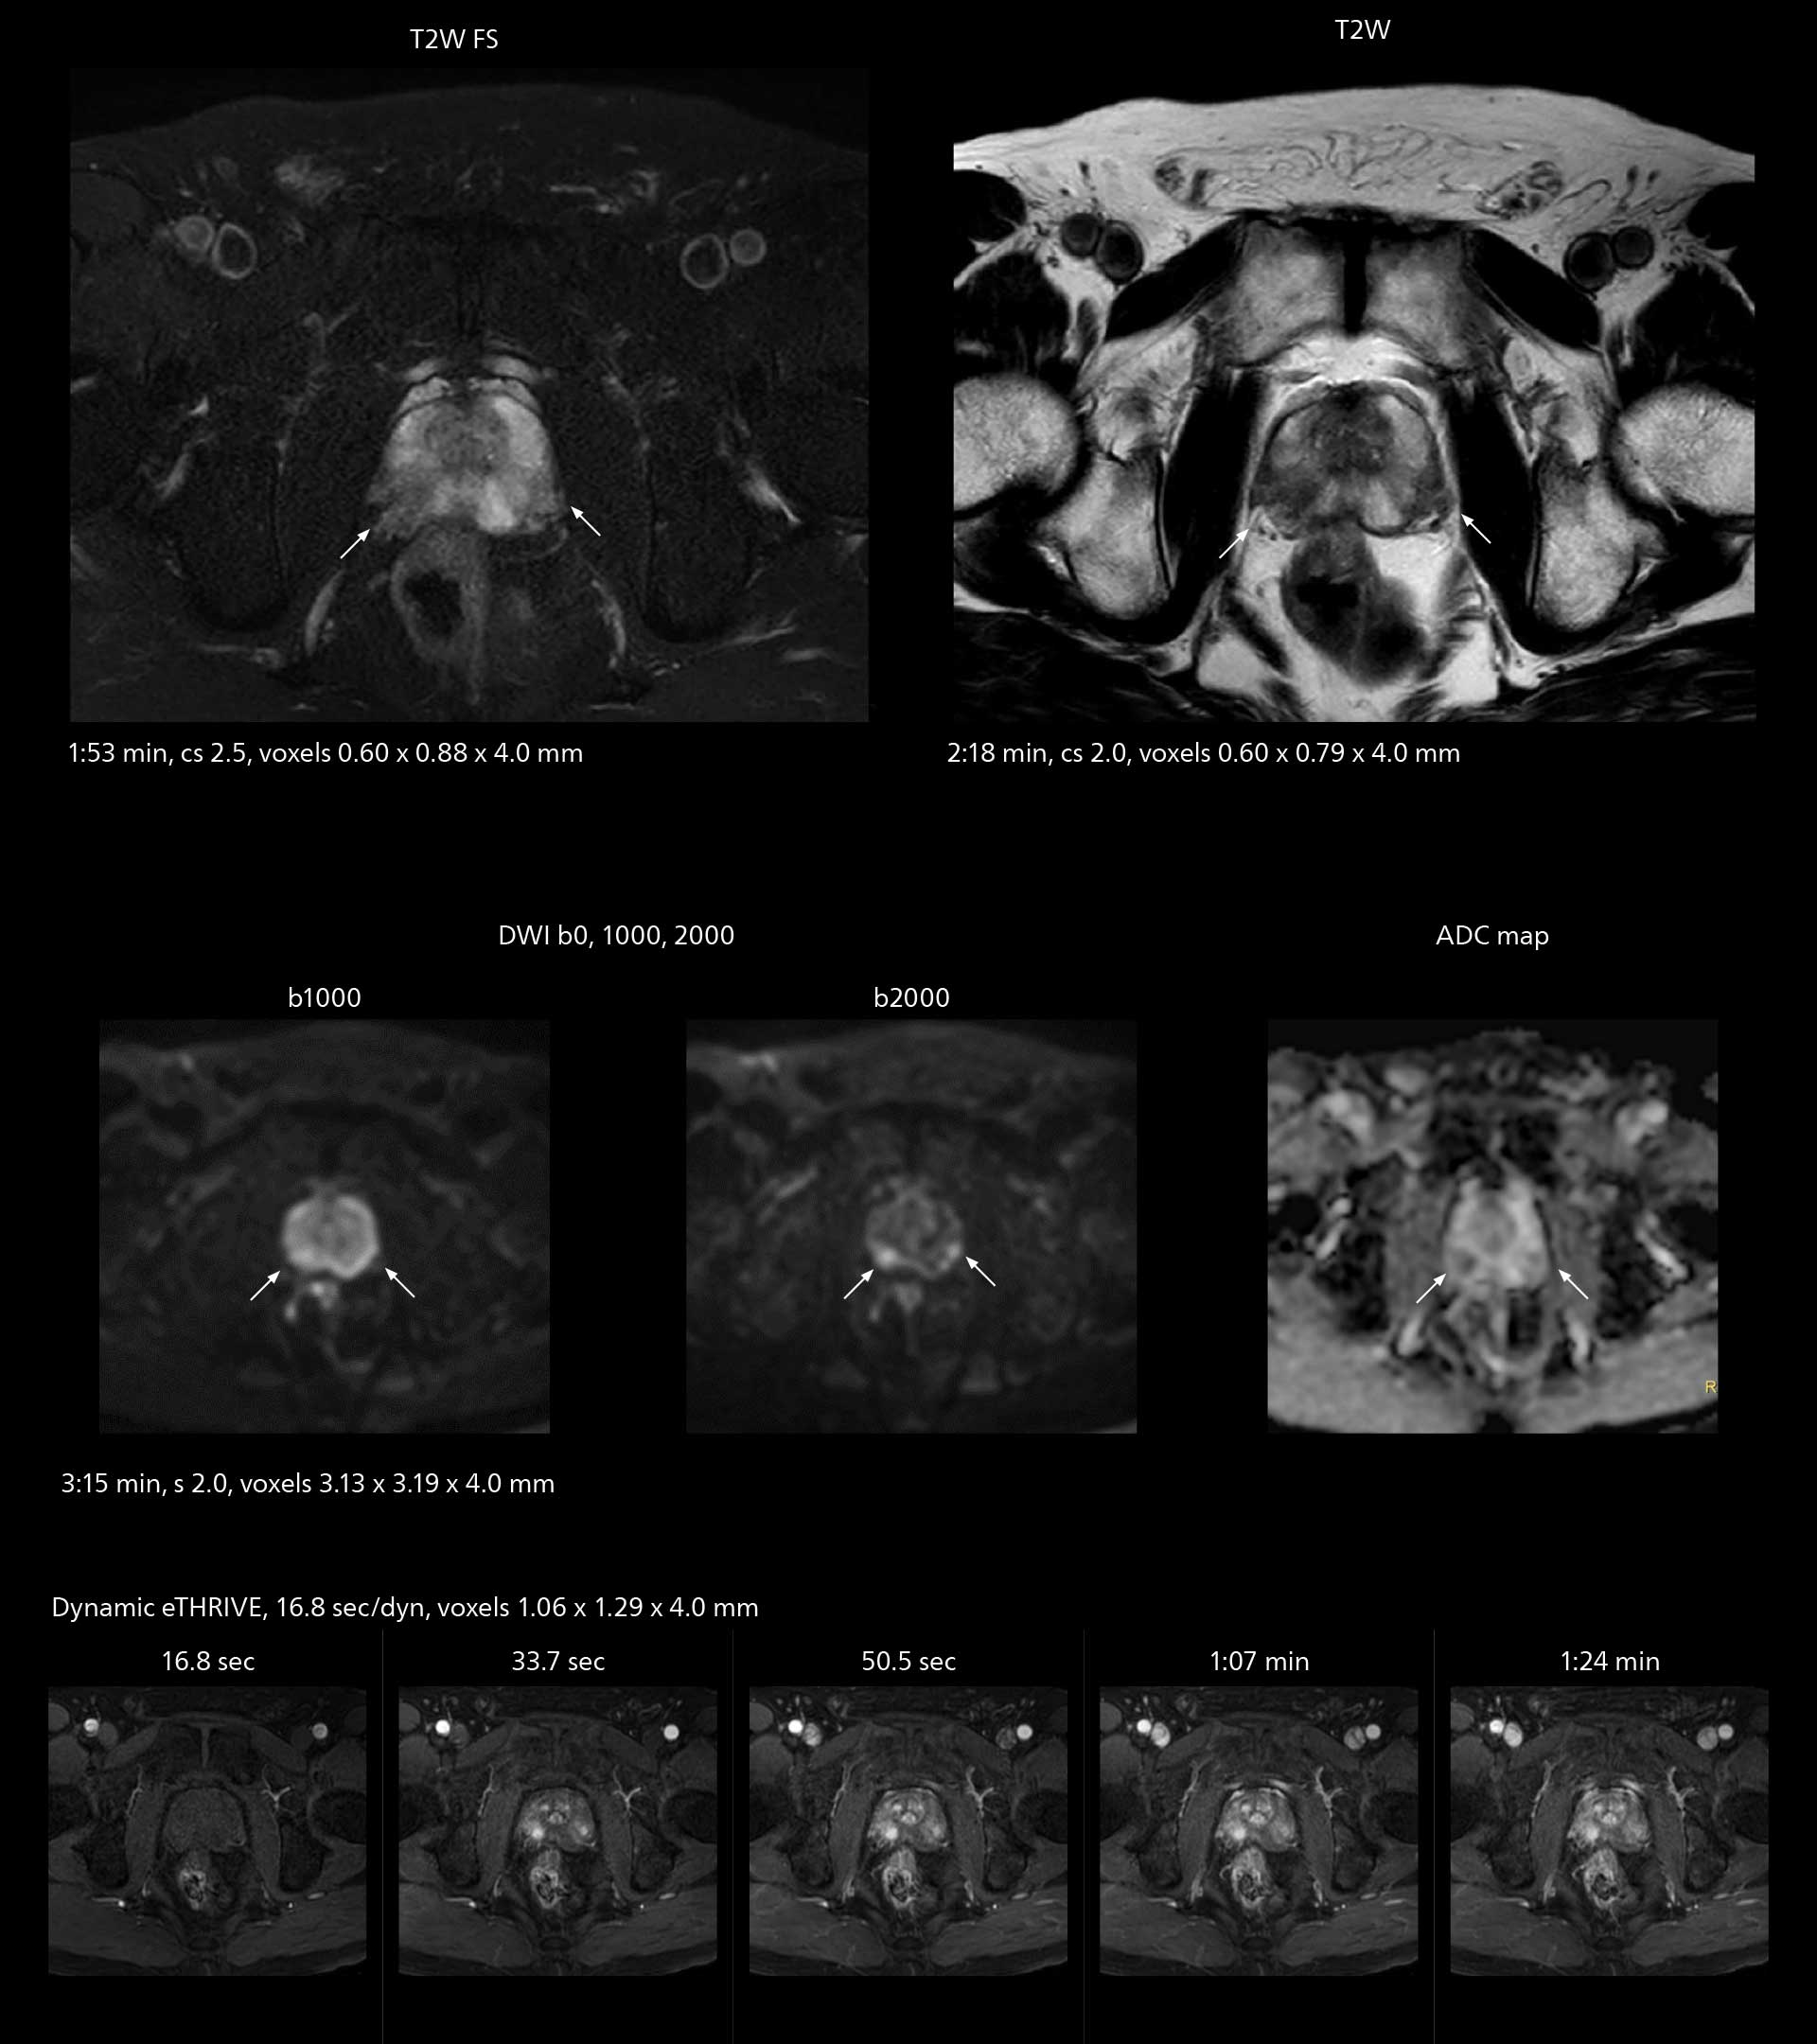

Diffusion studies benefit from powerful gradients

The high performance of the Vega HP gradients is particularly impressive in DWI. “The Vega HP gradients enable us to scan faster and use b-values as high as 2000, for example in prostate DWI and in DWIBS, which provides image quality that is remarkably improved over the previous system and we are able to more easily see lesions.”

MRI of prostate

Examples of prostate imaging showing faster scan times and improved resolution illustrate the power of SmartPath to Elition X in this case of prostate cancer with PI-RADS score 4.

The value of the Elition X gradients is also evident in DWIBS studies. “The fact that we can consistently obtain distortion‐free DWIBS while reducing imaging time at three coronal stations is excellent,” Dr. Makuuchi says. “In these patients, it’s also important that the application of Compressed SENSE to T2‐weighted, STIR and mDIXON sequences has no impact on the examination time of whole‐body imaging. As a result of the increased speed and higher image quality we realize, DWIBS studies have now become routine examinations.”